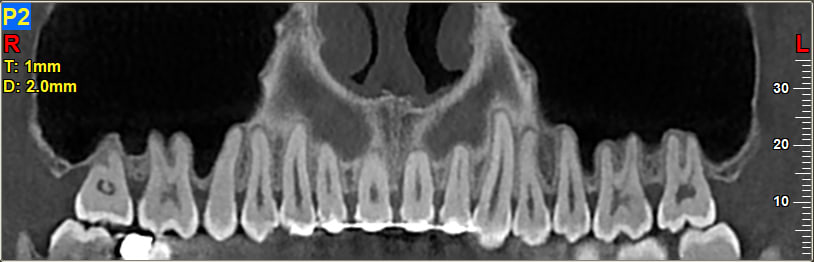

On m'a diagnostiqué une poche parodontale importante (en pensant qu'il s'agit d'un parodontite locale) à la 21, suite à consultation chez le Paro, on m'oriente vers un implant... Touché par la nouvelle mais pas abattu, je fais donc un scanner d'usage avant toute intervention, le radiologue indique sur son rapport :

"Présence d'une récession osseuse diffuse avec d'assez nombreuses lésions angulaires et poches parodontales sur toute l'arcade du maxillaire"

En effet, les clichés sont assez révélateurs. Le praticien a donc fait le constat suivant :

J'attache une vue coupe scan, d'autres clichés possibles si nécessaire.

Et c'est pas une pano ça c'est une coupe scan

Ramène au moins une pano et une rétro de la 21, sur ta coupe scan on ne voit pas grand chose, mais je serai d'avis que rien n'est perdu (et même question pourquoi un implant sur 21 ???).

Avant tout : une coupe de scanner n'est en aucun cas adaptée ni même utilisable pour poser un diagnostique parodontal. Une pano non plus d'ailleurs si on veut être précis. En gros si tu as une pathologie paro monstrueuse ok on la verra sur n'importe quelle radio mais c'est pas du tout le cas sur ce que tu nous montres ici.

Si tu veux une réponse claire il faut des retroalveolaires et un sondage paro, sans ca impossible de te répondre et ceux qui s'y risquent doivent être devins. Va donc consulter un autre parodontiste exclusif pour un 2ème avis et tu seras fixé.

Concernant la rhizalyse de la 17 évoquée plus haut, je vois vraiment pas comment on peut se prononcer sur une coupe de scanner... Il suffit que la dent ait un axe qui fait que l'apex sort de la coupe et HOP, on le voit plus et la dent semble bonne pour la poubelle alors que tout va bien. Là encore, une pano ou une retroalveolaire seraient bien plus utiles, en tout cas il est clairement impossible de dire quoi que ce soit avec la coupe du scan.